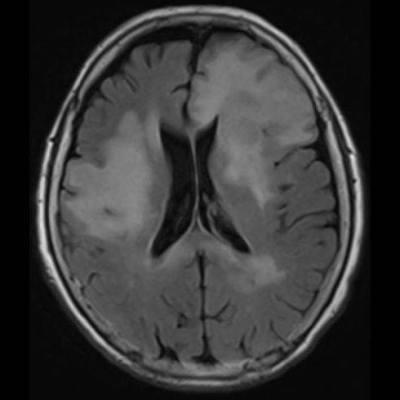

- (A) Her iki periventriküler beyaz cevherde aksiyel T2A, FLAIR serilerde hiperintens, T1A hipointens geniş ödem alanları (oklar) izlenmektedir. Sol frontalde T2A’da hipointens kitle lezyonuna (ok) dikkat ediniz.

- Genellikle supratentoriyal alanda, bazal ganglion, periventriküler beyaz cevher, orta hat ve korpus kallozum vb. yerleşme eğiliminde tek veya multipl kitleler şeklinde görülür.

- Kitleler çoğunlukla solid ve homojendir.

- MRG’de, lenfomalar tipik olarak T2A sekanslarda hipointens olup DAG’de belirgin difüzyon kısıtlanması gösterirler.